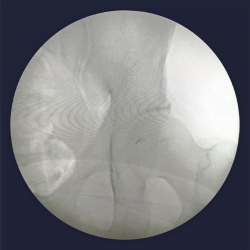

Contrast dye spread of piriformis